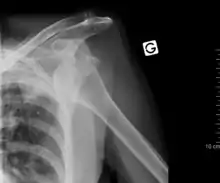

كثيراً ما يشتبه تشخيص لخلع الكتف استناداً إلى تاريخ المريض والفحص البدني. يتم إجراء الصور الشعاعية لتأكيد التشخيص. معظم الاضطرابات في مفصل الكتف تظهر في الصور الشعاعية . قد يكون من الصعب الكشف بالصور الشعاعية بأخذها من المنظر الامامى للخلع الخلفي، ولكن يمكن أخذها بسهولة في الوضعيات الأخرى. بعد رد الكتف المخلوع عادة ما تتكرر الصور الشعاعية للتأكد من النجاح في رد الكتف والكشف عن الأضرار العظمية. بعد الخلع المتكرر للكتف يمكن استخدام التصوير التصوير بالرنين المغناطيسي النووي لتقييم الضرر الأنسجة اللينة. في ما يتعلق بالخلع المتكرر للكتف، يتم اجراء اختبار مفيد في تحديد الرياضيين الذين مهيئون لخلع الكتف مستقبلا". يوجد ثلاث أنواع منه : أمامى، خافى، سفلى .

العلاج

ينبغي التماس العلاج الطبي الفوري للخلع المشتبه فيه. عادة، يتم الاحتفاظ بالكتف في موضعه الحالي باستخدام جبيرة أو حبال، قد توفر الدعامة وسادة بين الذراع والجذع وزيادة الراحة. ايضا المسكنات القوية ضرورية لتهدئة الألم والشدة المرتبطة به.

يقوم الاطباء برد المفصل المخلوع إلى مكانه بطريقتين هما: أليز، هيبوكرات.